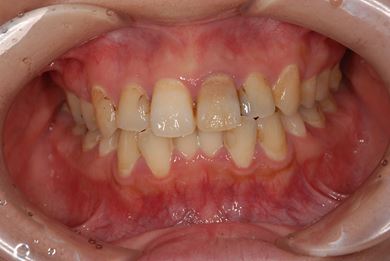

性別/年齢 女性 / 26歳

主訴 虫歯や汚れの治療を希望。

治療方針 セラミック治療にて、審美的回復を行う。

治療前

• 治療前